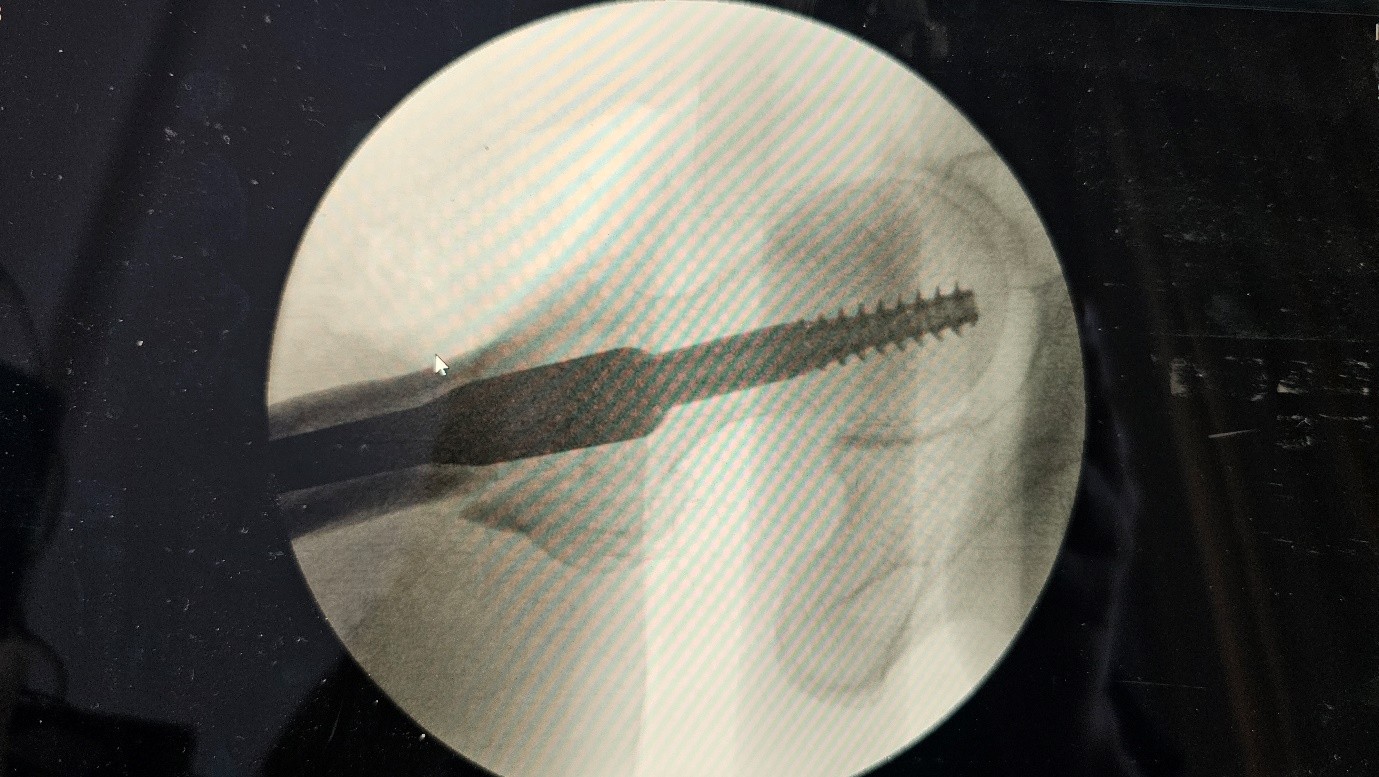

Postoperative X-rays were inconclusive due to suboptimal views. To evaluate screw position and fracture alignment more accurately, a CT scan was performed. The CT revealed that the cephalic screw had cut through the femoral neck, protruding medially outside the cortex, and continued into the femoral head—confirming a case of cut-through.

Planned Revision:

Anatomical fracture reduction

Use of a medial-posterior nail entry point

Placement of the cephalic screw in a central–central position within the femoral head to optimize mechanical stability

Revision surgery :

Fig 6

Fig 7

Figure 5

Figure 6

Figure 7